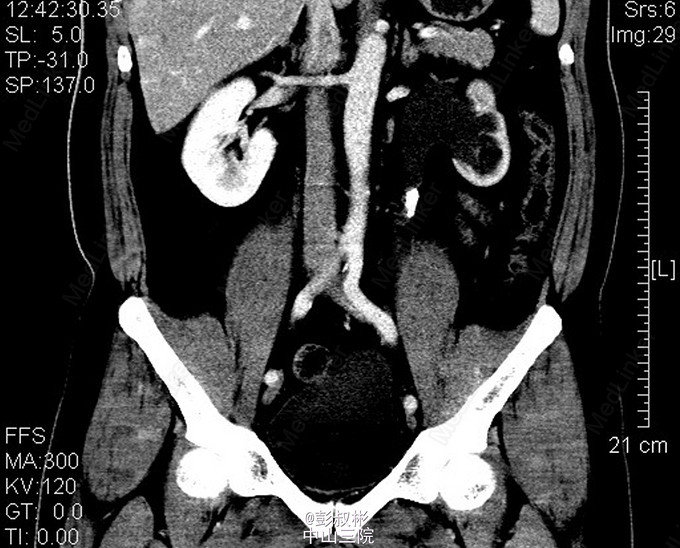

男性,37岁,体检发现左输尿管结石2月。泌尿系彩超:左输尿管上段结石并左肾积液。腹部平片:左输尿管上段结石。腹部CT:左输尿管上段结石,大小约18×12×9mm,左输尿管上段及左肾盂积水,左肾功能减退。